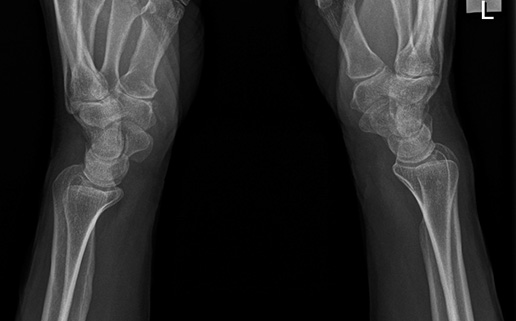

Are the markers of anatomical side always used in radiography? Wstęp: Właściwe oznaczenie strony pacjenta na radiogramie stanowi istotny aspekt wykonania zdjęcia rentgenowskiego, umożliwiający prawidłową identyfikację i ocenę badanych struktur. Nieprawidłowa lateralizacja uznawana jest za błąd jakościowy mogący skutkować niewłaściwym postępowaniem terapeutycznym. Cel: Celem badań była analiza prawidłowości stosowania lateralizacji w rentgenodiagnostyce klasycznej. Materiał i metody: Wykonano analizę 338 kolejnych radiogramów zrealizowanych w…